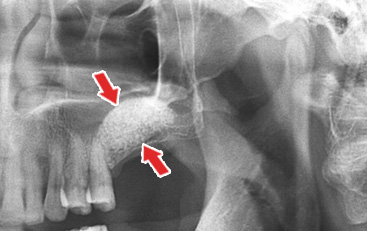

2 »ó¾Çµ¿ »ÀÀÌ½Ä ÈÄ

»ó¾Çµ¿À» °Å»óÇÑ ÈÄ »ÀÀ̽ÄÇÏ¿© ³ôÀ̰¡ Áõ°¡ÇÑ ¸ð½À